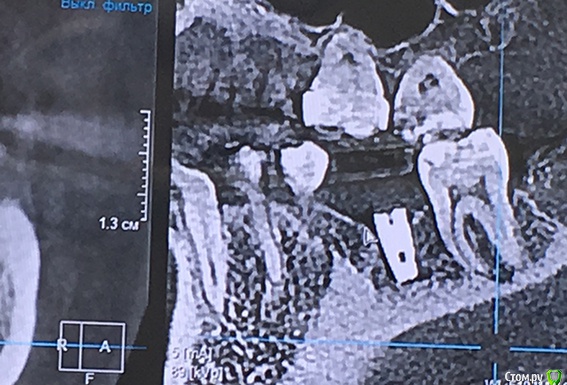

Naminutku Опубликовано 22 марта, 2019 Поделиться Опубликовано 22 марта, 2019 Уважаемые форумчане, прошу вашей помощи в сложившейся ситуации.Сразу отмечу, что нет цели кого-то уличить в непрофессиональности, есть цель разобраться в ситуации и принять правильное решение относительно дальнейшего лечения. Установлено 2 имплантата АльфаБио 3,3х8мм. Один в районе жевательного зуба, второй в зоне резца.По ряду обстоятельств после имплантации я обратилась в другую клинику за консультацией (в обеих клиниках причин сомневаться в профессионализме и добрых намерениях у меня нет)Во время консультации был сделан 3D снимок, на котором видно, что имплантат в районе жевательного зуба не полностью погружен в костную ткань и расположен на 2мм выше края кости. В районе резца имплантат выходит за пределы костной ткани (см. снимки)Врач считает, что в обоих случаях имплантаты установлены некорректно. В районе жевательного зуба в последующем мягкие ткани разрушатся и выступающая часть имплантата будет торчать, а в районе резца очень высока вероятность развития воспаления и разрушения костной ткани, + из-за особенностей позиционирования, коронку придется делать со смещением (т.е. центральные оси коронки и имплантата не будут совпадать), что вместе приведет к недолговечности всей этой истории. Предложения 2:1. оставить как есть, закончить лечение и решать проблемы по мере возникновения.2. пока имплантаты не успели намертво врасти в кость (срок чуть больше месяца), убрать, восстановиться и поставить новые имплантаты.Мне очень важно мнение профессионалов в данной ситуации. Насколько критична ситуация, стоит ли удалять, заново имплантировать или проблемы с существующими имплантатами нет? Ссылка на комментарий

red_butler Опубликовано 22 марта, 2019 Поделиться Опубликовано 22 марта, 2019 Ничего критичного я на снимках не увидел... Ссылка на комментарий

koreandr Опубликовано 22 марта, 2019 Поделиться Опубликовано 22 марта, 2019 Тоже ничего критичного не вижу Ссылка на комментарий

suballex Опубликовано 25 марта, 2019 Поделиться Опубликовано 25 марта, 2019 Плюсую. На данный момент, критических изменений нет. Ссылка на комментарий